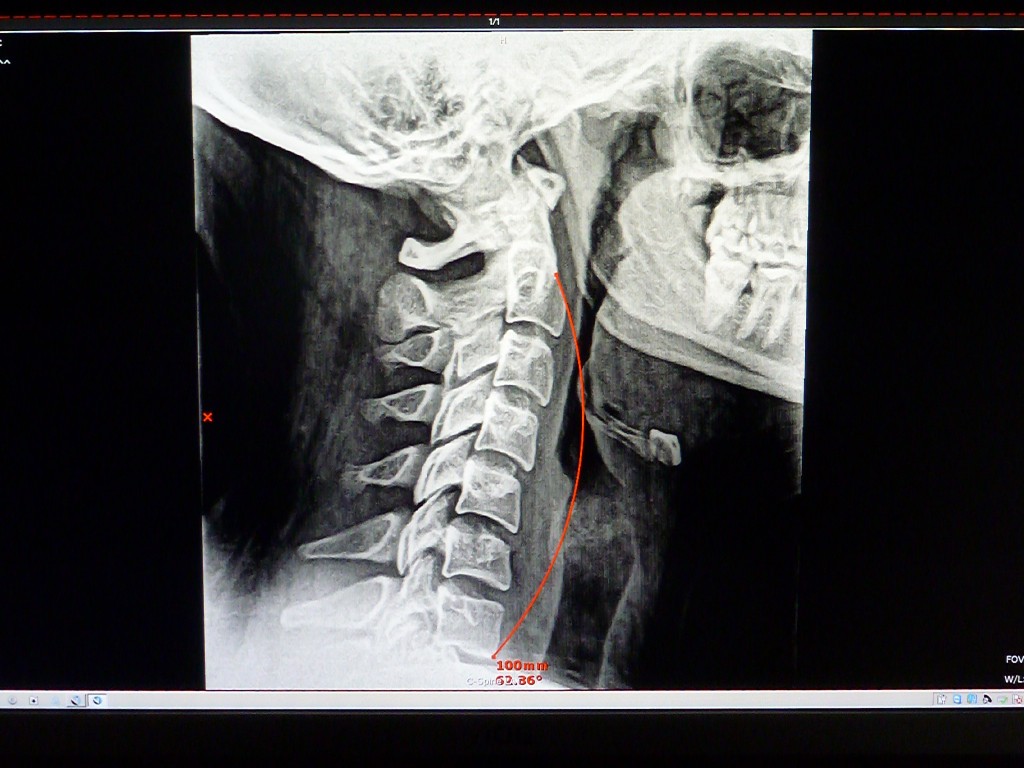

Digital X-rays Now Available at Our Office

We are happy to announce that we have upgraded our x-ray equipment and now have a state-of-the-art digital system. From what we understand we are the only chiropractic office in the Roanoke Valley with the advanced DR system. This amazing technology will allow us to provide our patients with much better x-rays. With better quality, we can improve diagnosis (for example, fractures or arthritis). Also, we will easily be able to make copies of x-rays on a CD for patients when they request them.